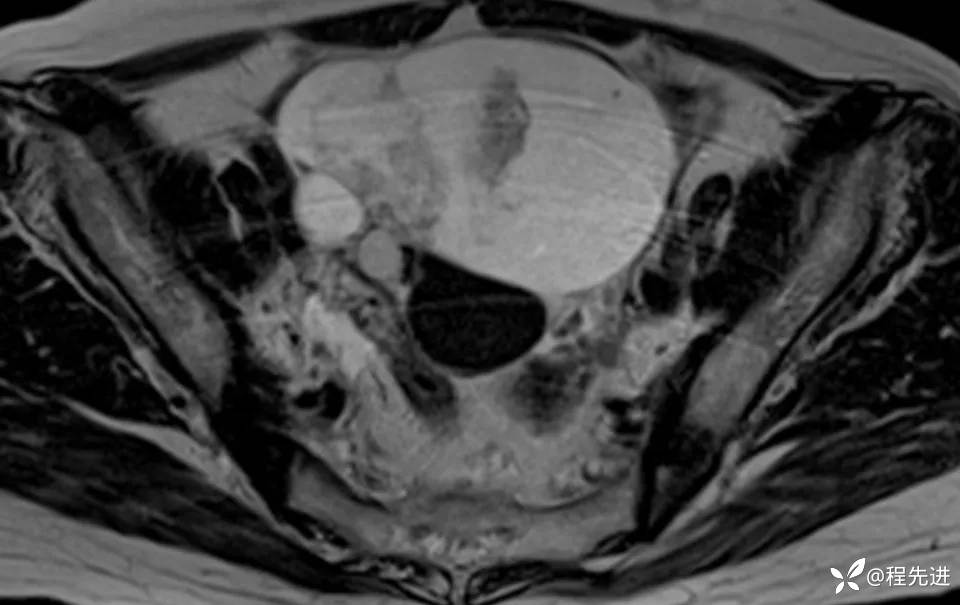

MRI平扫+增强: